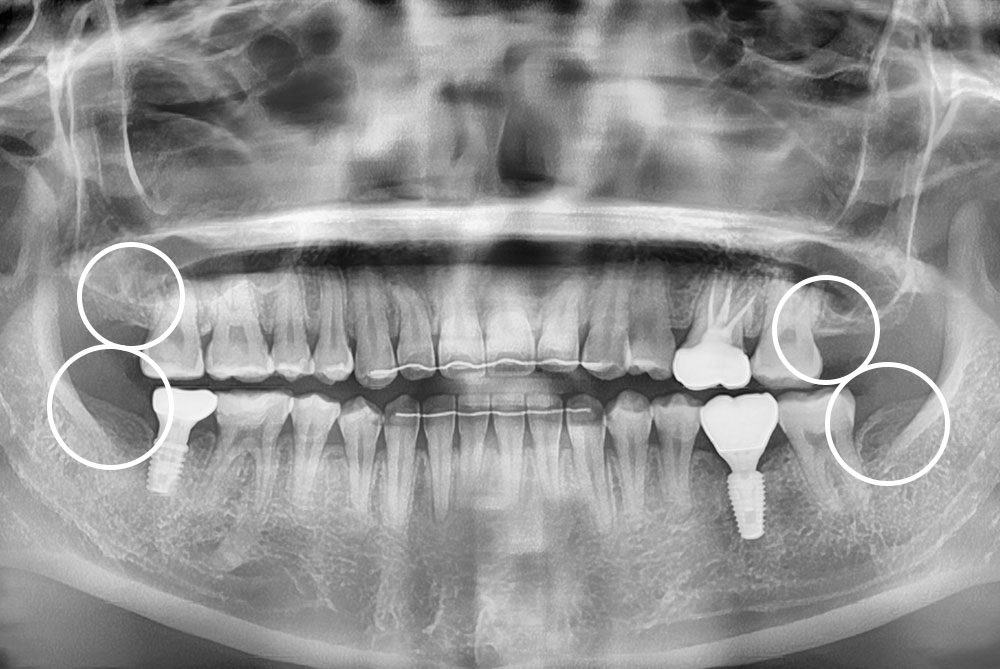

[사랑니] 매복 사랑니 발치

치료전 : 2022-09-05